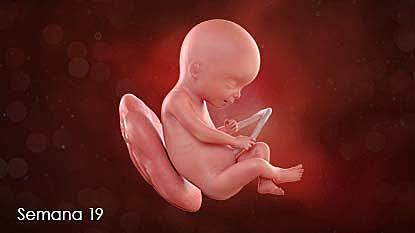

• Semana 19

19

Semana 19

-El sistema nervioso central se empieza a desarrollar rápidamente, sobre todo aquellas áreas destinadas a los sentidos del gusto, el olfato, la audición, la visión y el tacto (Algunos estudios indican que el bebé ya puede oír).

-Empiezan las etapas de sueño y de actividad.